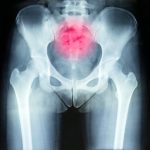

Sacroiliac (SI) joint pain dysfunction: Causes of lower back, buttock, and hip pain

SI joint pain, or pain in the sacroiliac joints found between the pelvis and the base of the spine, can be felt in the lower back and buttocks and occurs for a variety of reasons. Continue reading to find out which symptoms to look out for and how SI joint pain is diagnosed and treated.

SI joint pain most often begins in the lower back and buttocks and is typically only on one side of the body. The pain can reach up to the lower hip, groin, and upper thigh as well. Numbness, tingling, and weakness in the affected leg are also symptoms associated with SI joint pain. These symptoms can worsen when sitting, sleeping, walking, or using stairs. Those with SI joint pain may also find it painful to ride in a car. Continue reading…